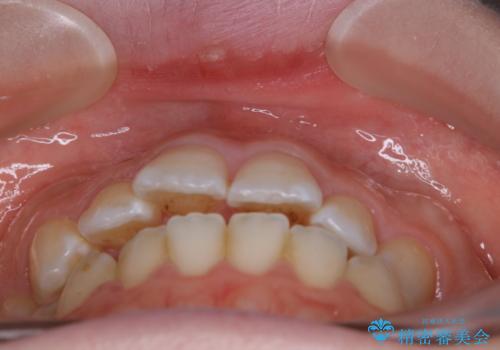

【非抜歯】上下の前歯が噛み合わないオープンバイトの治療

骨格的な問題もあり、噛んだ時に奥歯しか当たらず前歯の被蓋があまりない状態でした。

臼歯の位置が高く噛んだ時に奥歯しか当たらなかったり、舌癖などが原因で前歯が前に倒れてしまうことで上下の前歯の被蓋がなくなってしまっている状態をオープンバイトといいます。

前者の場合は臼歯を圧下し沈めてあげることで改善させます。後者の場合は前方に傾斜している歯を元の角度に戻してあげることで改善しますが、舌癖がある場合はその癖自体を無くす治療をしない限りまた同じ状態へと後戻りしてしまいます。